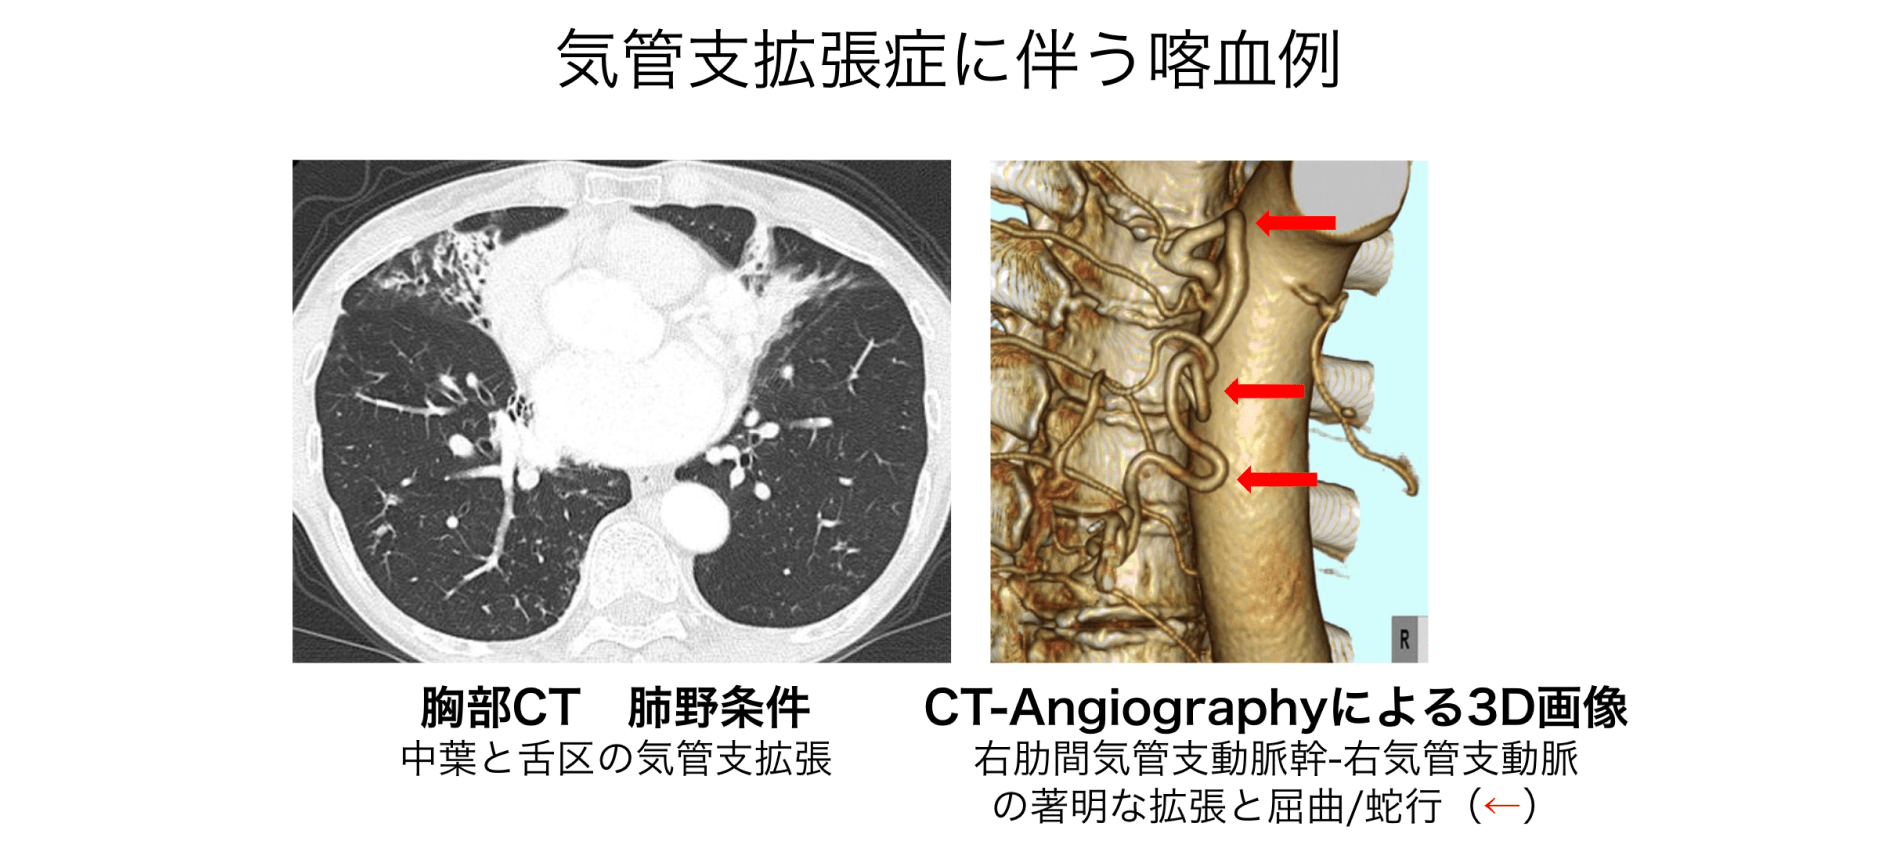

CTパターンから理解する呼吸器疾患: 所見×患者情報から導く鑑別と治療 | 門田 淳一 |本 | 通販 | Amazon,

CTパターンから理解する呼吸器疾患: 所見×患者情報から導く鑑別と治療 | 門田 淳一 |本 | 通販 | Amazon, 国立病院機構 東京病院―幅広い呼吸器疾患に対し、専門的で緻密な診療を提供 | メディカルノート,

国立病院機構 東京病院―幅広い呼吸器疾患に対し、専門的で緻密な診療を提供 | メディカルノート, 呼吸器外科疾患について | 藤田医科大学岡崎医療センター 呼吸器外科,